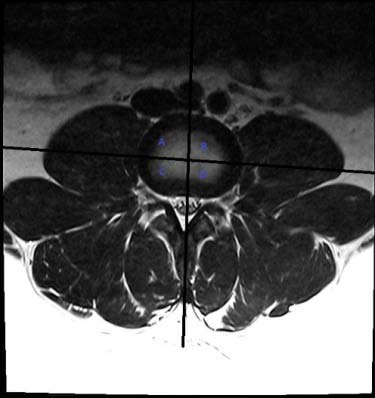

The analytic process was three-fold: a) search for disc herniation in the three lower lumbar discs, with emphasis of its location central or lateral, 2) assess the attachment of the PM muscle to both sides of the disc, and verify if the attachment was present, partial, or absent (nonattachment), and 3) verify whether there was disc herniation and partial or absent attachment of the PM muscle to the same disc. To facilitate the assessment of the PM muscle adherence to the disc's borders, and to correctly locate the herniated disc, the disc's surface was divided into four quadrants of equal size. The four quadrants were obtained by drawing two perpendicular lines at the center of the disc (Figure 1). The quadrants were named: right anterolateral, left anterolateral, right posterior, and left posterior. When the muscle fascicles adhered to the disc in all four quadrants, it was considered as complete attachment (Figure 1). The lack of contact of the PM muscle fascicles with the disc border in one, or two, or three quadrants was defined as partial attachment (Figure 2a). The lack of contact of the PM muscle fascicles to the disc in all four quadrants was defined as total absence of attachment or nonattachment (Figure 2b).